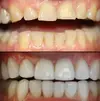

Zirconium Applications

Porcelain Applications

Laminate Veneer